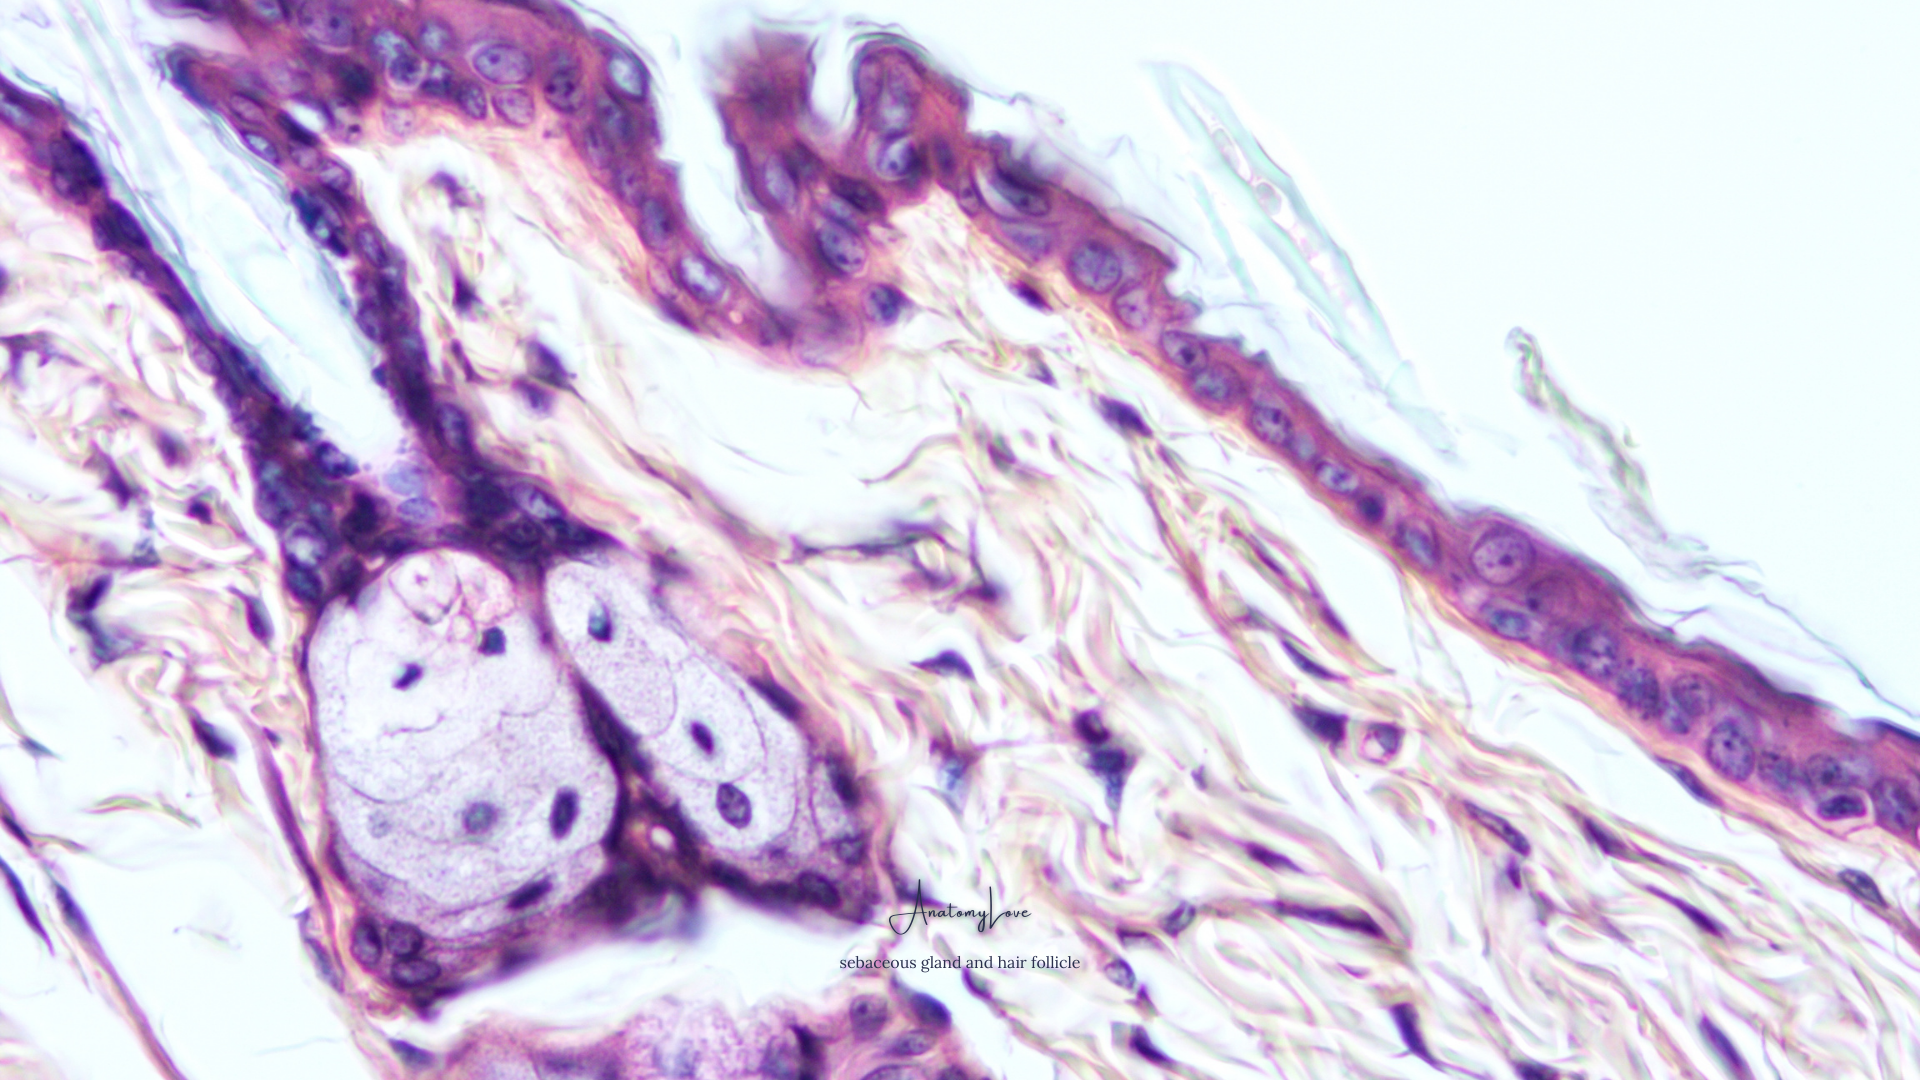

There are so many beautiful micrographs - with the pinks and purples typical of H&E staining, alongside beautiful blues from a trichrome stain, or the golden and gray hues of silver or golgi stains. In this set of wallpapers, we'll see osteocytes, ovaries, liver lobules, the cerebellum, gastric mucosa, multiple presentations of bone, smears of blood cells, the renal cortex and medulla, appendix, salivary gland, skin, nerves, the esophagus, various cartilage, large intestine, vessel walls, neurons, connective tissues, lung, taste buds on the tongue, and good 'ol fat cells.